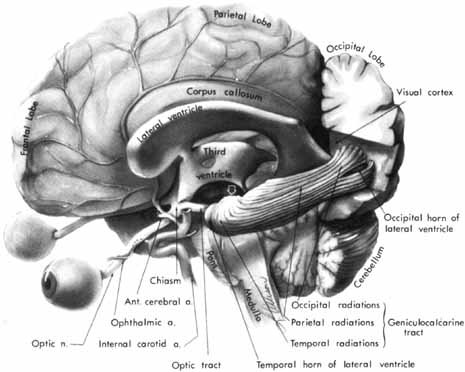

The human primary visual sensory system comprises the retina, optic nerves, optic chiasm, optic tracts, lateral geniculate nuclei, geniculostriate radiations, striate cortex, visual association areas, and related interhemispheral connections. This specialized afferent system lies principally in a horizontal plane that crosses at right angles the major ascending sensory and descending motor systems of the cerebral hemispheres (Fig. 1). The anterior portion of the visual system is intimately related to the vascular and bony structures at the skull base and undersurface of the brain. The posterior portions are closely applied to the lateral aspects of the ventricular system that extend throughout the cerebral hemispheres. Thus, defects of the visual pathways, as revealed by visual field assessment or otherwise, have great localizing value in neurologic diagnosis. The dominant role of vision in humans may be expressed numerically by considering, for example, the number of axons in the human optic nerve (700,000 to 1.4 million) as compared with axons in the acoustic nerve (approximately 31,000).1 Thus, the ratio of afferent neurons in the peripheral visual apparatus to the number in the aural system is roughly 40 to 1.

Fig. 1 The visual-sensory system. The left cerebral hemisphere has been removed, with the exception of the occipital lobe and the ventricular system. The left lateral geniculate body is hidden (arrow). Note the following relationships: optic nerve with internal carotid and anterior communicating arteries, chiasm in the floor of third ventricle, forward sweep of temporal radiations around lateral ventricle, course of occipital radiations toward interhemispheral surface of occipital lobe. The cerebral falx and cerebellar tentorium are not illustrated.